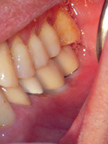

左下顎完成兩大臼齒之補綴,核對咬合。

左上顎第一、第二小臼齒缺損。